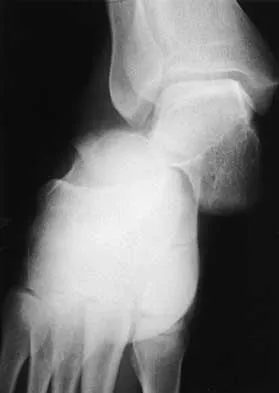

A 19-year-old woman has had a painful prominence on the lateral border of her fifth metatarsal head since she was a young girl. Nonsurgical management, including the use of a wide toe box shoe, has failed to provide relief. Examination reveals a callus over the lateral prominence and on the plantar portion as well. A clinical photograph and a radiograph are shown in Figures 34a and 34b. Treatment should consist of

The type of deformity described is a type 2 bunionette. There is often a congenital component to this deformity. The bowing of the fifth shaft differentiates a large intermetatarsal angle from a type 3 deformity. A distal chevron osteotomy corrects 1 degree in the intermetatarsal angle for every 1-mm shift. Because of limitations in the width of the fifth metatarsal neck, the allowable shift is generally 3 to 4 mm. This shift will not compensate for the large intermetatarsal angle. The floating osteotomy has a high rate of delayed union/nonunion and a low satisfaction rate. Metatarsal head excision has a high complication rate, including severe shortening, transfer metatarsalgia, stiffness, and pain. A more proximal procedure is necessary to correct the large intermetatarsal angle and the lateral bowing. The osteotomy of choice is a diaphyseal shaft osteotomy. Because this patient has a plantar callosity and a lateral callosity, the osteotomy is angled superiorly to elevate the fifth shaft with the shift, eliminating overload of the plantar metatarsal head and subsequent callus formation. Shereff MJ, Yang QM, Kummer FJ, Frey CC, Greenidge N: Vascular anatomy of the fifth metatarsal. Foot Ankle 1991;11:350-353. Coughlin MJ: Treatment of bunionette deformity with longitudinal diaphyseal osteotomy with distal soft tissue repair. Foot Ankle 1991;11:195-203.